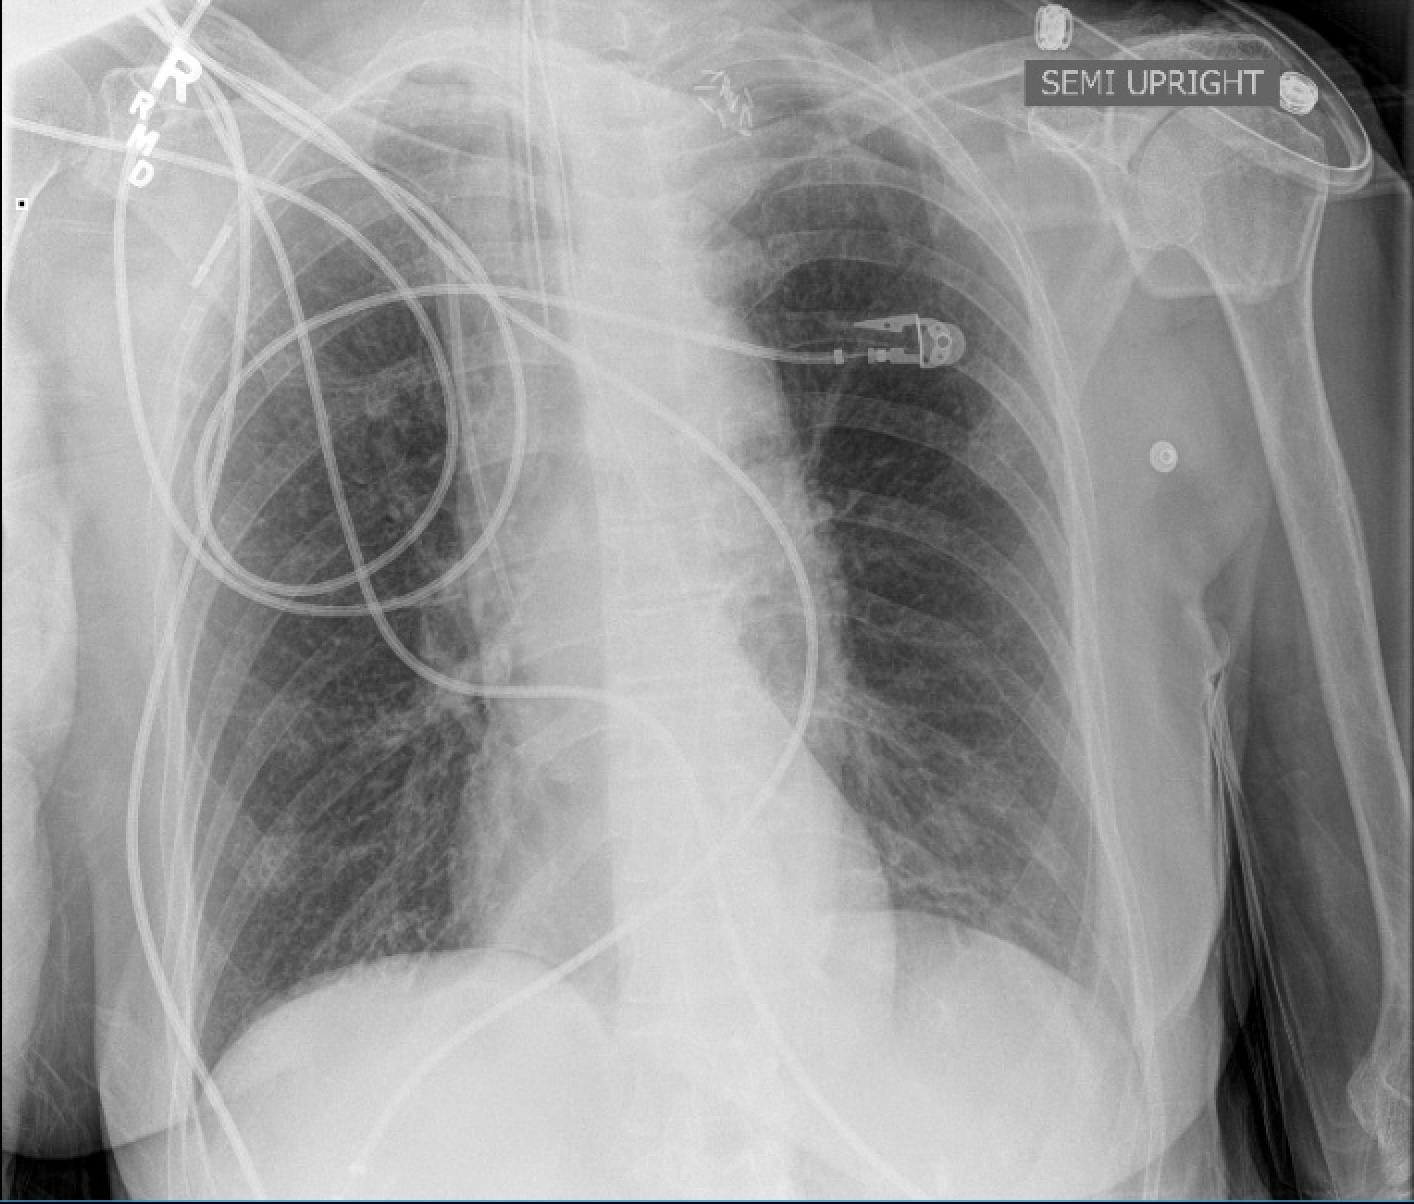

Tracheal deviation due to iatrogenic carotid pseudoaneurysm

History

The patient is an 80 year old woman with lung cancer who was getting a port placed at her home institution. It was to be a left subclavian venous port, but when access was not gained, a left internal jugular venous port was attempted, but after the intitial stick and sheath placement, pulsatile bleeding was recognized and the sheath removed. Hemostasis was achieved with clips and the wound closed and a right internal jugular venous port was placed. The postprocedural CXR shown above showed tracheal deviation and numerous clips from the initial port placement attempt, and a CT scan with contrast (unavailable) showed a carotid pseudoaneurysm of 3cm projecting posteriorly behind the pharynx/esophagus. She was kept intubated and sedated, and transferred for management.

On examination, her vital signs were stable. She had 2cm of tracheal deviation and swelling was apparent at the base of the neck. While my trainees may be better versed at this than I at the particulars of this, my old general surgery trauma training kicked in, as she had a Zone I neck carotid injury, neck zones.pngwhich in my experience is highly morbid despite how stable the patient was. Point again to trainees, this is no different from someone having stabbed this patient with a knife at the base of the neck. My options were: